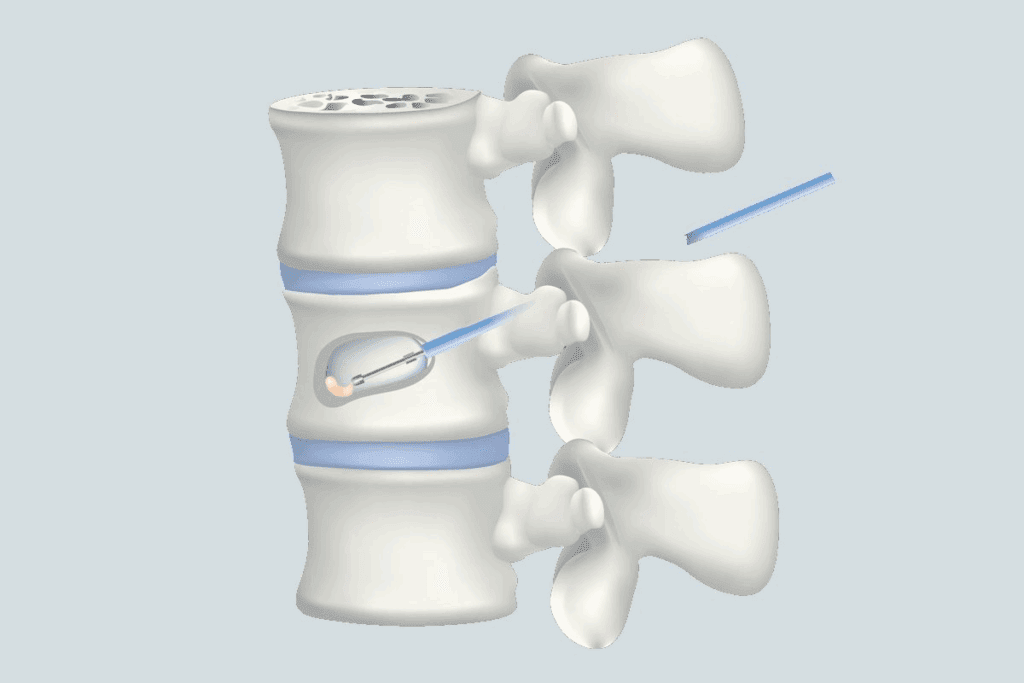

Epidural Steroid Injections for L5 S1 Disk Protrusion Treatment

Epidural steroid injections are a helpful treatment for L5 S1 disk protrusion. They aim to reduce inflammation and ease pain in the lower back and legs. Let’s dive into how these injections work and their benefits for L5 S1 disk protrusion.

How Epidural Injections Target Pain

Epidural steroid injections put anti-inflammatory medicine near the spinal cord. This method helps lessen swelling and irritation around the nerves. It can greatly reduce pain and improve movement for those with L5 S1 disk protrusion.

“Epidural steroid injections are precise, targeting the inflamed area directly,” says a pain management expert. “They can offer quicker relief than oral medications, which is great for those who haven’t seen results from other treatments.”

Procedure Details and Expectations

The procedure is done under X-ray to ensure the medicine goes exactly where it needs to. Patients lie on their stomach, and the area is cleaned and numbed. Then, a thin needle injects the medicine into the epidural space.

Most people can go back to normal activities a few hours after. Some might feel sore at the injection site. Relief can start in a few days or take up to two weeks for some.

Effectiveness for Different L5 S1 Conditions

Epidural steroid injections work for many L5 S1 issues, like disk protrusion and herniation. But, how well they work can depend on the condition and the person. Many patients find significant pain relief, but how long it lasts can vary.

It’s important to remember these injections aren’t a cure. They’re part of a bigger treatment plan that might include physical therapy and lifestyle changes. Like any treatment, there are risks and side effects to consider with a healthcare provider.

In summary, epidural steroid injections are a valuable option for L5 S1 disk protrusion. They provide targeted pain relief and can improve life quality. Understanding the procedure and its benefits helps patients make informed choices about their care.